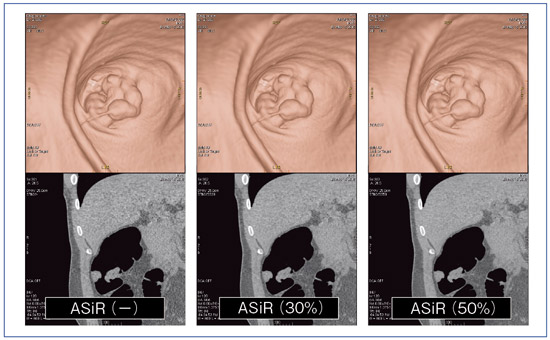

【大放出セール】 Amazon.co.jp: 大腸CTテキスト: 原理・特性の基礎知識から現場で 語学+参考書の詳細情報

Amazon.co.jp: 大腸CTテキスト: 原理・特性の基礎知識から現場で。大腸CT検査~実務・症例・基礎知識~: イチから学ぶ! | 東海。大腸CT検査 | 医療法人 山下病院|愛知県一宮市の消化器内科。 現在、1名がこの商品を検討中です

撮影から読影までを網羅した東芝の大腸CT技術について - 東芝

撮影から読影までを網羅した東芝の大腸CT技術について - 東芝

大腸CTテキスト:原理・特性の基礎知識から現場で使えるセッティング,読影法まで消化管先進画像診断研究会

大腸CTテキスト:原理・特性の基礎知識から現場で使えるセッティング,読影法まで消化管先進画像診断研究会